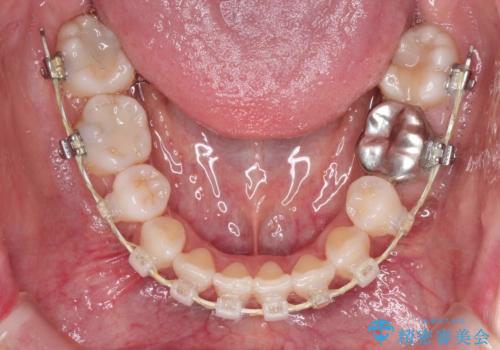

ハーフリンガル抜歯矯正 八重歯を改善する

- ハーフリンガル

- 小臼歯4本抜歯によるハーフリンガル・ワイヤー矯正を計画した。